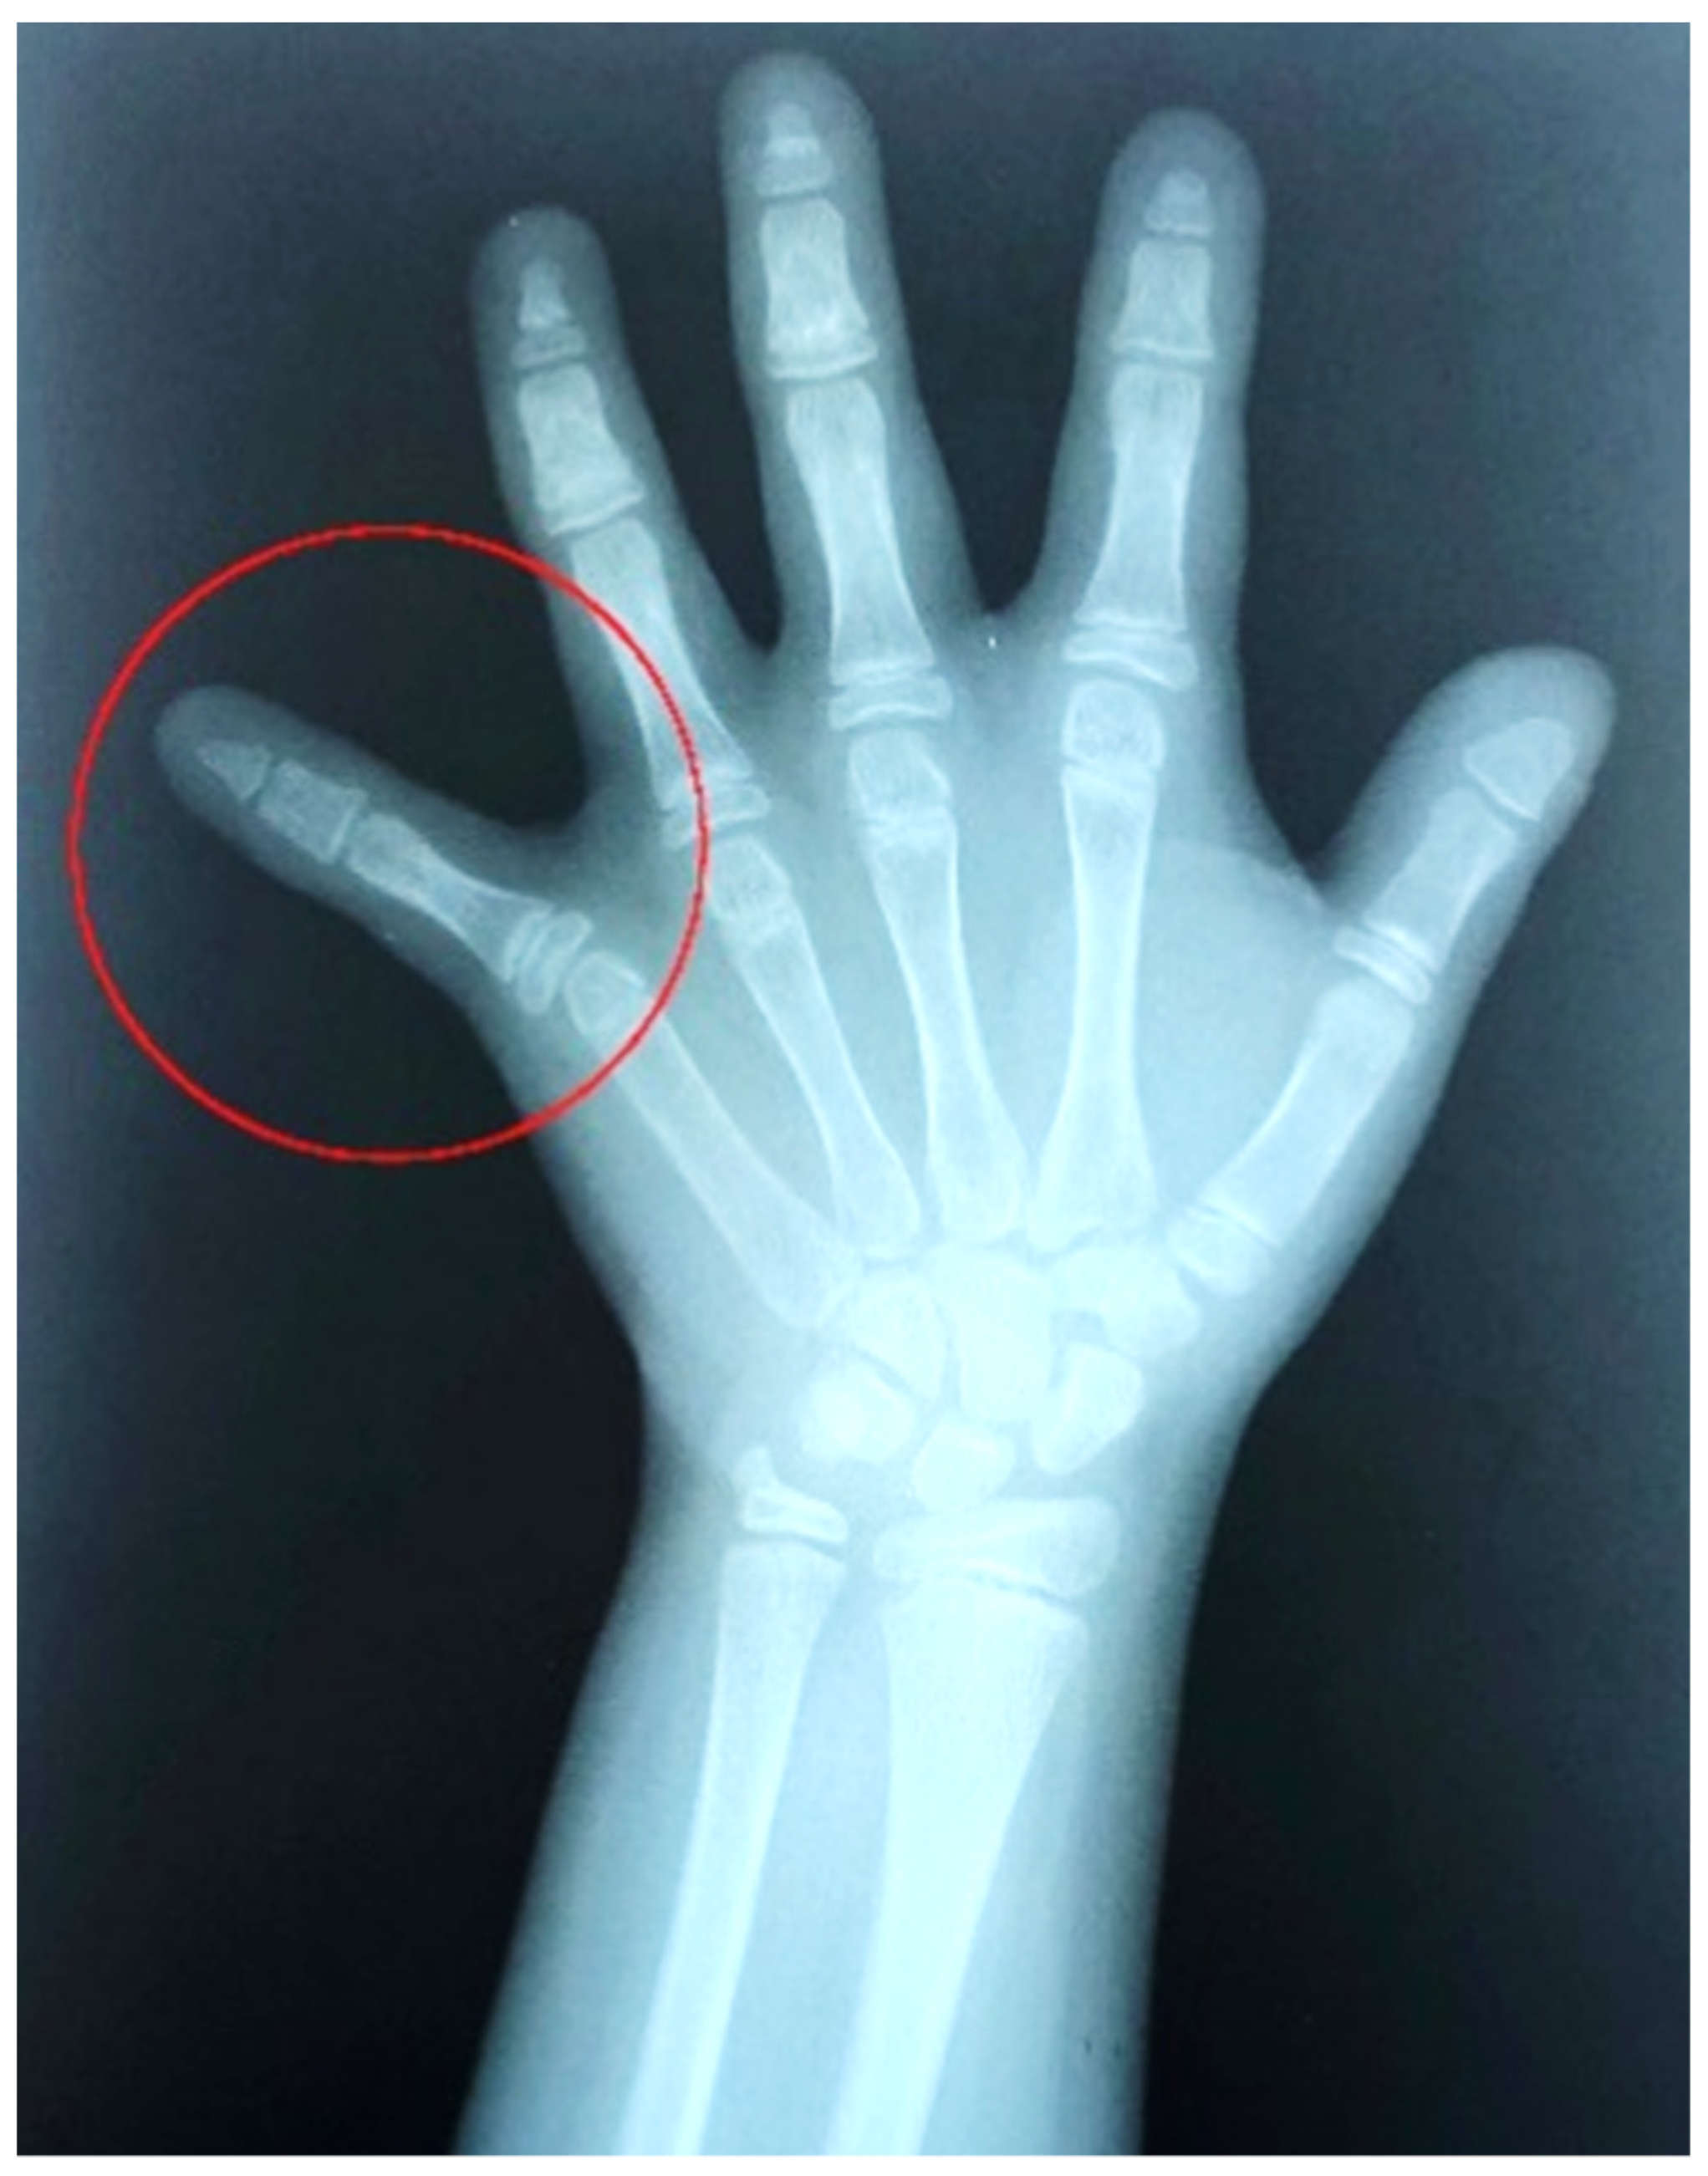

2. Clinical Report